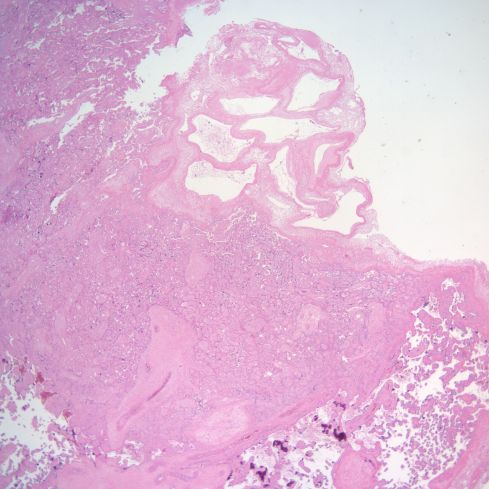

Thin walled vessels may show thrombi although many of these may be in venules (Figs 8, 9).

Fig 8: This sample of the parietal membranes is a transverse section with the amnion at the top. There is thrombus is a thin walled vessel with necrosis of the media. H&E 10x

Fig 9: This is another example of a thrombus in the parietal decidua showing a thrombus with medial necrosis of the vessel, likely a spiral artery. There is very early organization of the thrombus. H&E 20x

The significance of these later two findings is unknown.